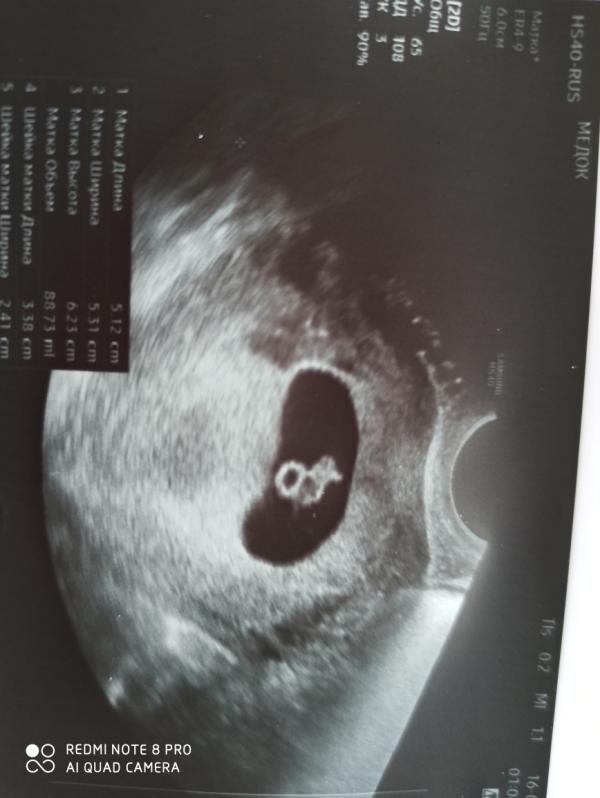

Ух, я сходила на УЗИ.

Одуван опережает свое развитие аж, по месячным у меня ровно 7 недель, а по УЗИ 7 недель и 4 дня 😆

Уже и амниотический мешок видно и сердечко стучит 😍😍😍

Сказали вставать на учет, получать свою молочку и приходить потом только на скрининг в июне.

Правда из за анамнеза отягченного сказали недели через две прийти и сердечко послушать. Ну ничего, сходим 😇

Дату родов рассчитали, я ржала 😅2 января, спасибо что не 1 😂😂😂

Такой уже красавец, даже ручки есть, уповаю что мелкий для м...